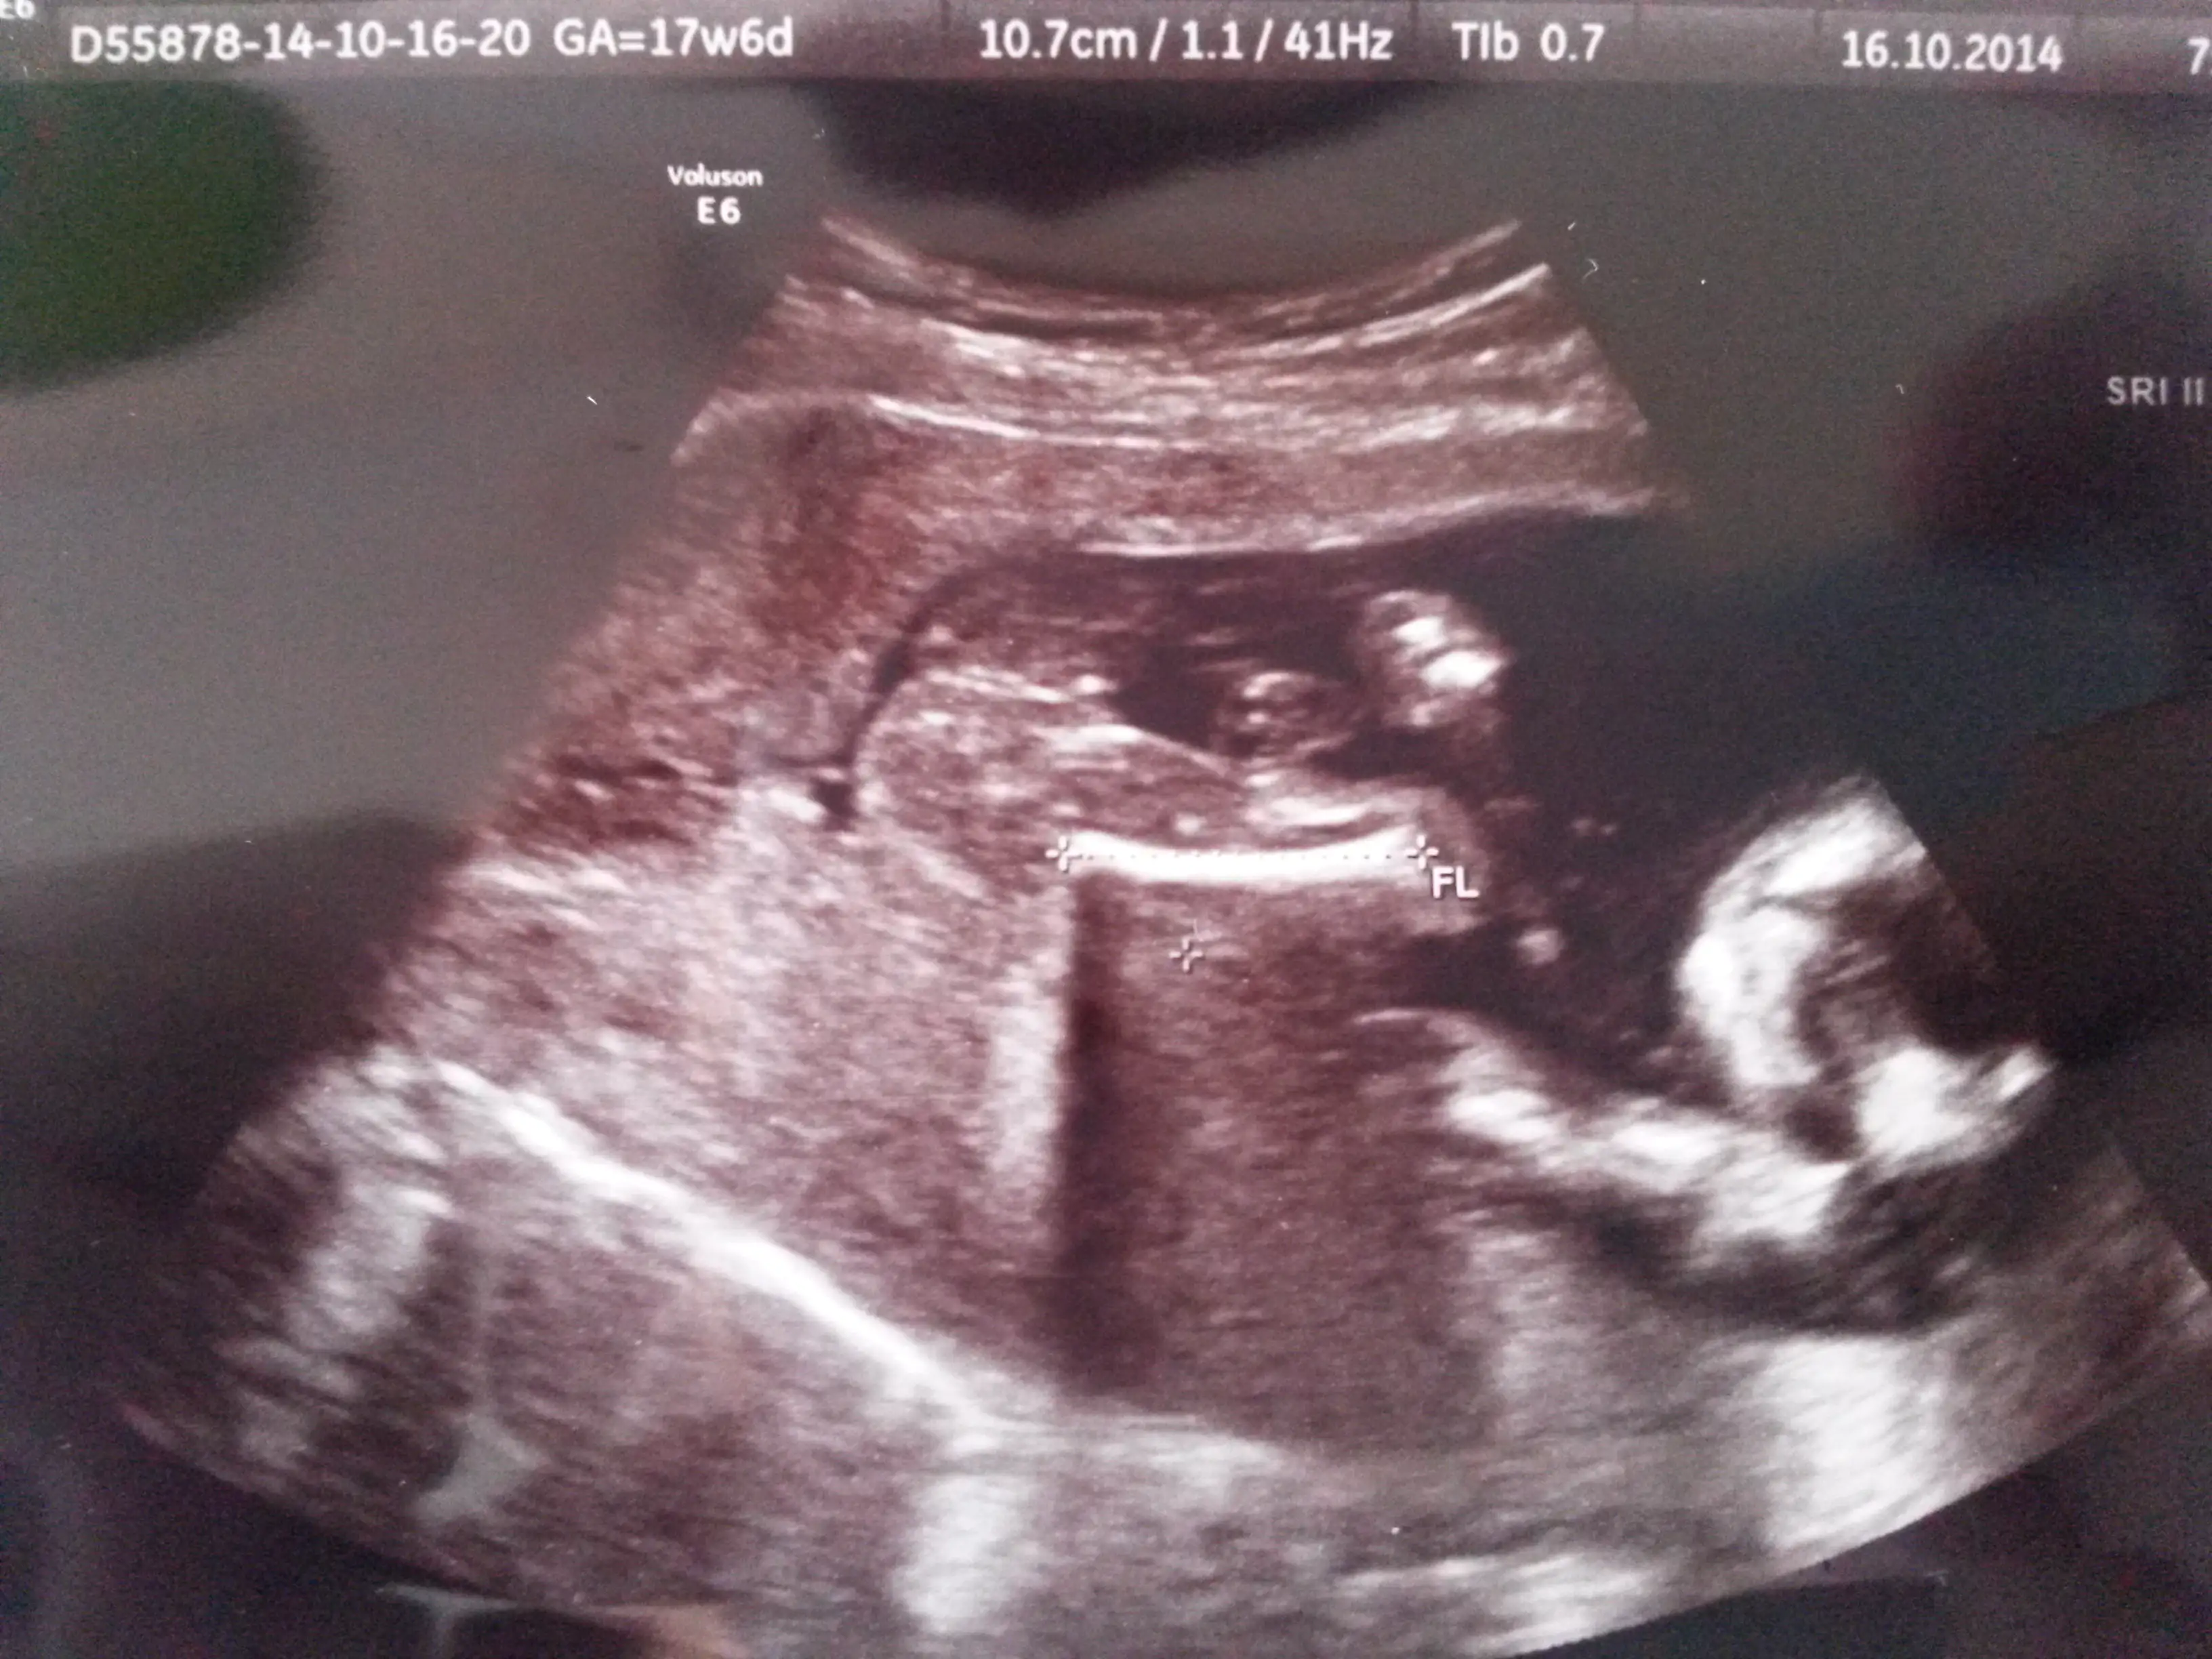

Gozun aydin canim sag salim dogmasinida nasip etsin rabbim :)Günaydın kızlar, dün renkli dopplere girdim kesin artık bir kızım oluyor.. 458 gram olmuş yumruk yapmış ellerini ayak tabanını gördüm çok değişik bir duygu ama goruntuler cok net degıl cunku eşi bebeğin önündeymiş.. böbreklere kalbine gelen giden kan damarlarına baktılar Allaha şükür bir sıkıntı yokmuş.. 28 kasımda şeker yüklemesi için gidim hemde kontrole...